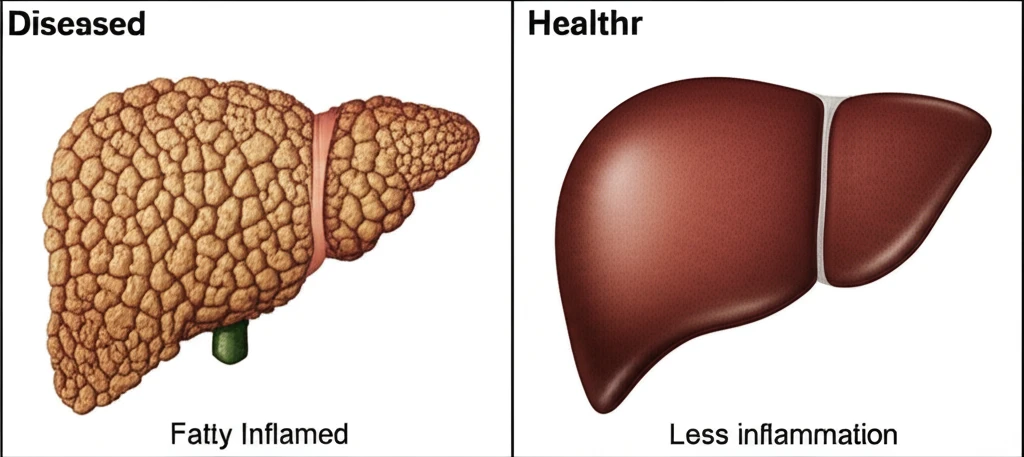

MASH 질환의 중요성

MASH(대사 기능 장애 관련 지방간염)는 치료하지 않고 방치할 경우 간경변, 간암과 같은 심각한 합병증으로 진행될 수 있는 질환입니다. 미국에서만 약 20명 중 1명에게 영향을 미치는 것으로 알려져 있습니다.

MASH는 미국에서 20명 중 1명꼴로 영향을 미치는 심각한 질병으로, 치료하지 않으면 간경변 및 간암으로 진행될 수 있습니다. 웨고비의 이번 승인은 이처럼 심각한 질병을 앓는 수많은 환자들에게 새로운 치료 희망을 제시할 것입니다.

이러한 웨고비의 성과는 MASH 치료 패러다임을 바꿀 잠재력을 가지고 있습니다. MASH는 미국에서 약 20명 중 1명에게 영향을 미치는 심각한 질병으로, 치료하지 않으면 간경변 및 간암으로 진행될 수 있습니다. 다음은 이번 승인의 주요 의미입니다.

이번 승인은 MASH 치료 분야에 새로운 지평을 열었습니다. 웨고비는 MASH 치료를 위해 승인된 최초이자 유일한 글루카곤 유사 펩타이드-1 수용체 작용제(GLP-1 RA)가 되었으며, 이는 미국에서 약 20명 중 1명에게 영향을 미치는 심각한 질병에 대한 치료 가능성을 크게 높였습니다. 치료하지 않으면 간경변 및 간암과 같은 심각한 결과로 진행될 수 있는 MASH의 진행을 억제하는 데 중요한 역할을 할 것으로 기대됩니다.

MASH란 무엇인가요?

MASH는 ‘비경변성 대사 기능 장애 관련 지방간염’을 의미하는 의학 용어입니다. 간에 지방이 축적되고 염증이 발생하는 질환으로, 적절히 관리되지 않으면 간 섬유화를 거쳐 심각한 합병증으로 이어질 수 있습니다.

주요 특징 및 진행 과정

- 간 내에 과도한 지방이 축적됩니다.

- 지방으로 인해 염증 반응이 발생합니다.

- 치료하지 않을 경우, 간경변 또는 간암으로 진행될 수 있습니다.

미국에서는 약 20명 중 1명에게 영향을 미칠 정도로 흔한 질병이지만, 치료제 개발은 더디게 진행되어 왔습니다.

따라서 이번 웨고비의 FDA 승인은 MASH 치료의 새로운 전환점이 될 것으로 기대됩니다.